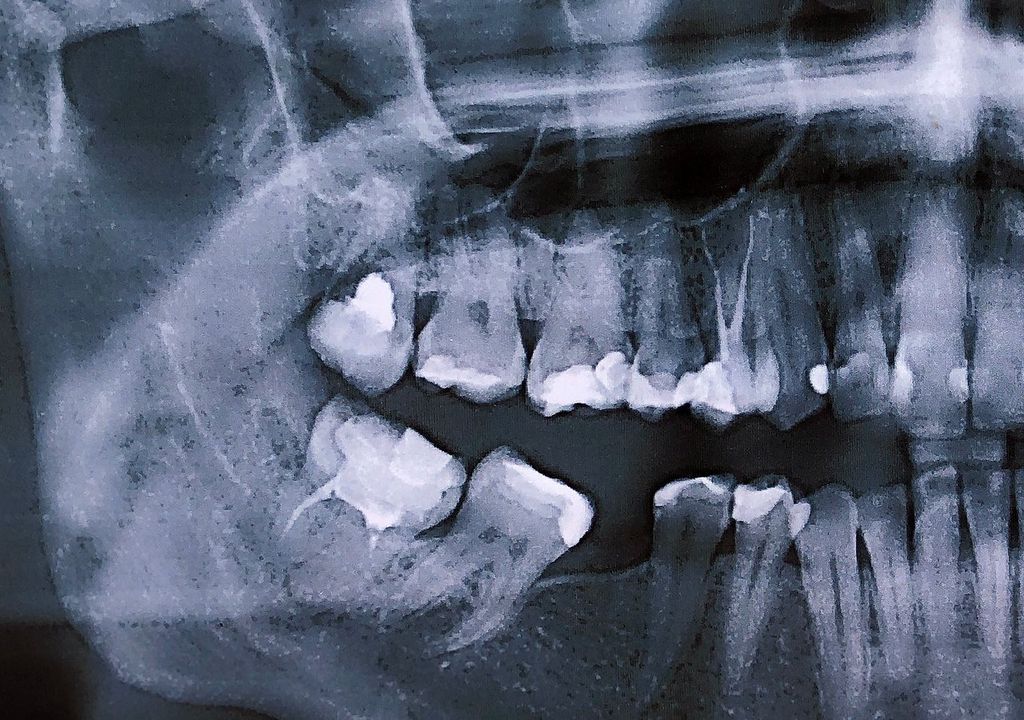

Una teoría más reciente plantea una posible explicación basada en la composición de los empastes dentales utilizados en ese período. Durante el siglo XIX, se empleaban varios metales, incluyendo estaño y plomo, para rellenar las cavidades dentales.

Si se usaban dos metales diferentes en la misma boca, esto podría crear una especie de "batería" en la boca de una persona. La mezcla de metales podría dar lugar a la electrólisis espontánea, generando gas dentro de un diente. Este gas podría haber causado la explosión del diente bajo ciertas condiciones, como la presión o la exposición al calor, como al fumar un cigarrillo.